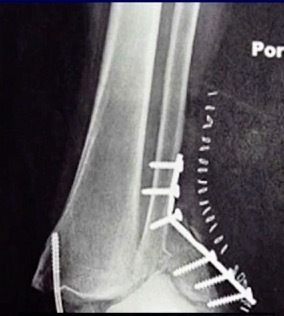

There’s much controversy in terms of should we wait or should we allow acute weight bearing following fixation of an unstable ankle fracture. Traditionally, patients were kept non-weightbearing for 6-12 weeks in some kind of cast or a boot. Nowadays, more contemporary approach is to allow earlier mobilization and protected weight bearing. Additionally, there’s many differences between North American and European schools of thought. When I give this talk to Europeans, they say “yeah we start immediate weight bearing all the time, that’s the standard.” But it’s certainly not the view in North America. I still see patients that have a beautiful x-ray with everything fixed and they’re kept in a cast for two months, which potentially defeats the whole point of surgical fixation. The benefit of surgery is to allow early mobilization and protected weight bearing. This practice can accelerate your patient’s return to work and return to life. However, nobody wants to see this x-ray in their clinic, especially with the staples still in (Figure 3).

This example is the fear that drives behavior amongst most orthopaedic surgeons who do not allow patients to move early.